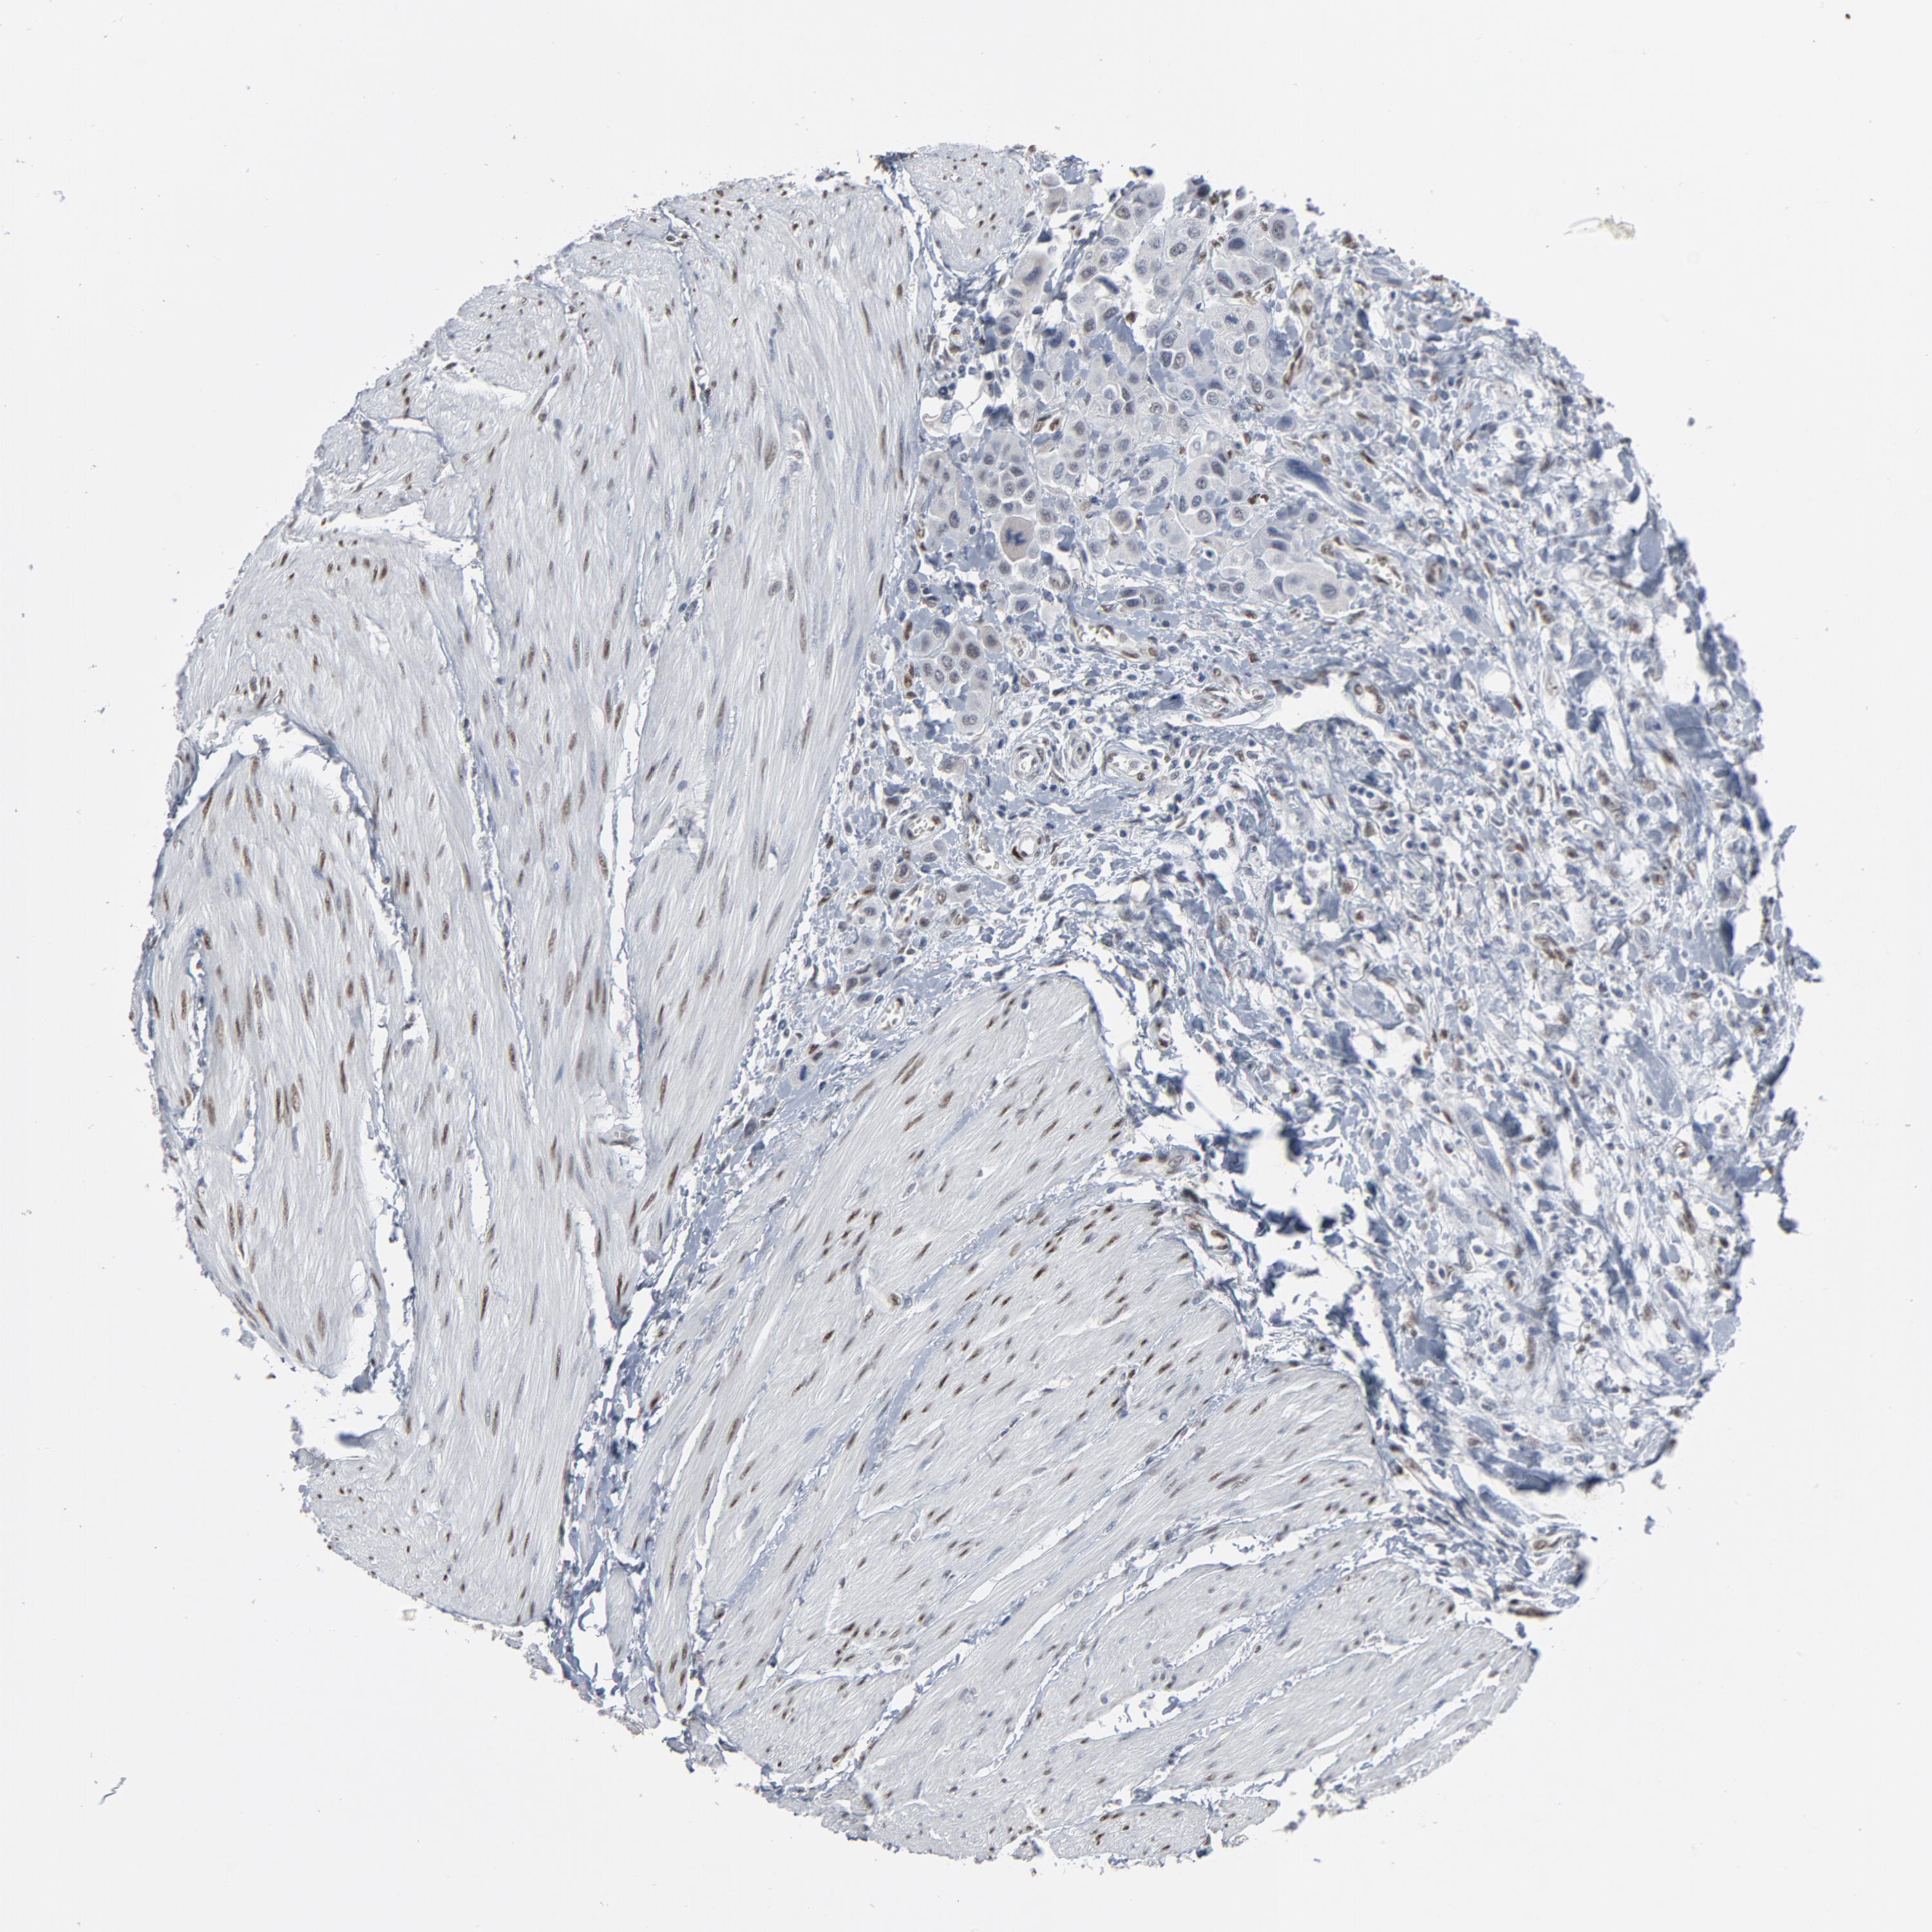

UROTHELIAL CANCER - Protein expressioni

A mouse-over function shows sample information and annotation data. Click on an image to view it in a full screen mode. Samples can be filtered based on level of antibody staining by selecting one or several of the following categories: high, medium, low and not detected. The assay and annotation is described here.

Note that samples used for immunohistochemistry by the Human Protein Atlas do not correspond to samples in the TCGA dataset.

Antibody stainingi

Antibody staining in the annotated cell types in the current human tissue is reported as not detected, low, medium, or high, based on conventional immunohistochemistry profiling in selected tissues. This score is based on the combination of the staining intensity and fraction of stained cells.

Each image is clickable and will lead to virtual microscopy that enables deeper exploration of all samples and also displays staining intensity scores, fraction scores and subcellular localization as well as patient and tissue information for each sample.

Antibody HPA003384

Staining

High

Medium

Low

Not detected

Intensity

Strong

Moderate

Weak

Negative

Quantity

>75%

75%-25%

<25%

None

Location

Nuclear

Cytoplasmic/membranous

Cytoplasmic/membranous,nuclear

Urothelial carcinoma, High grade

Urothelial carcinoma, Low grade